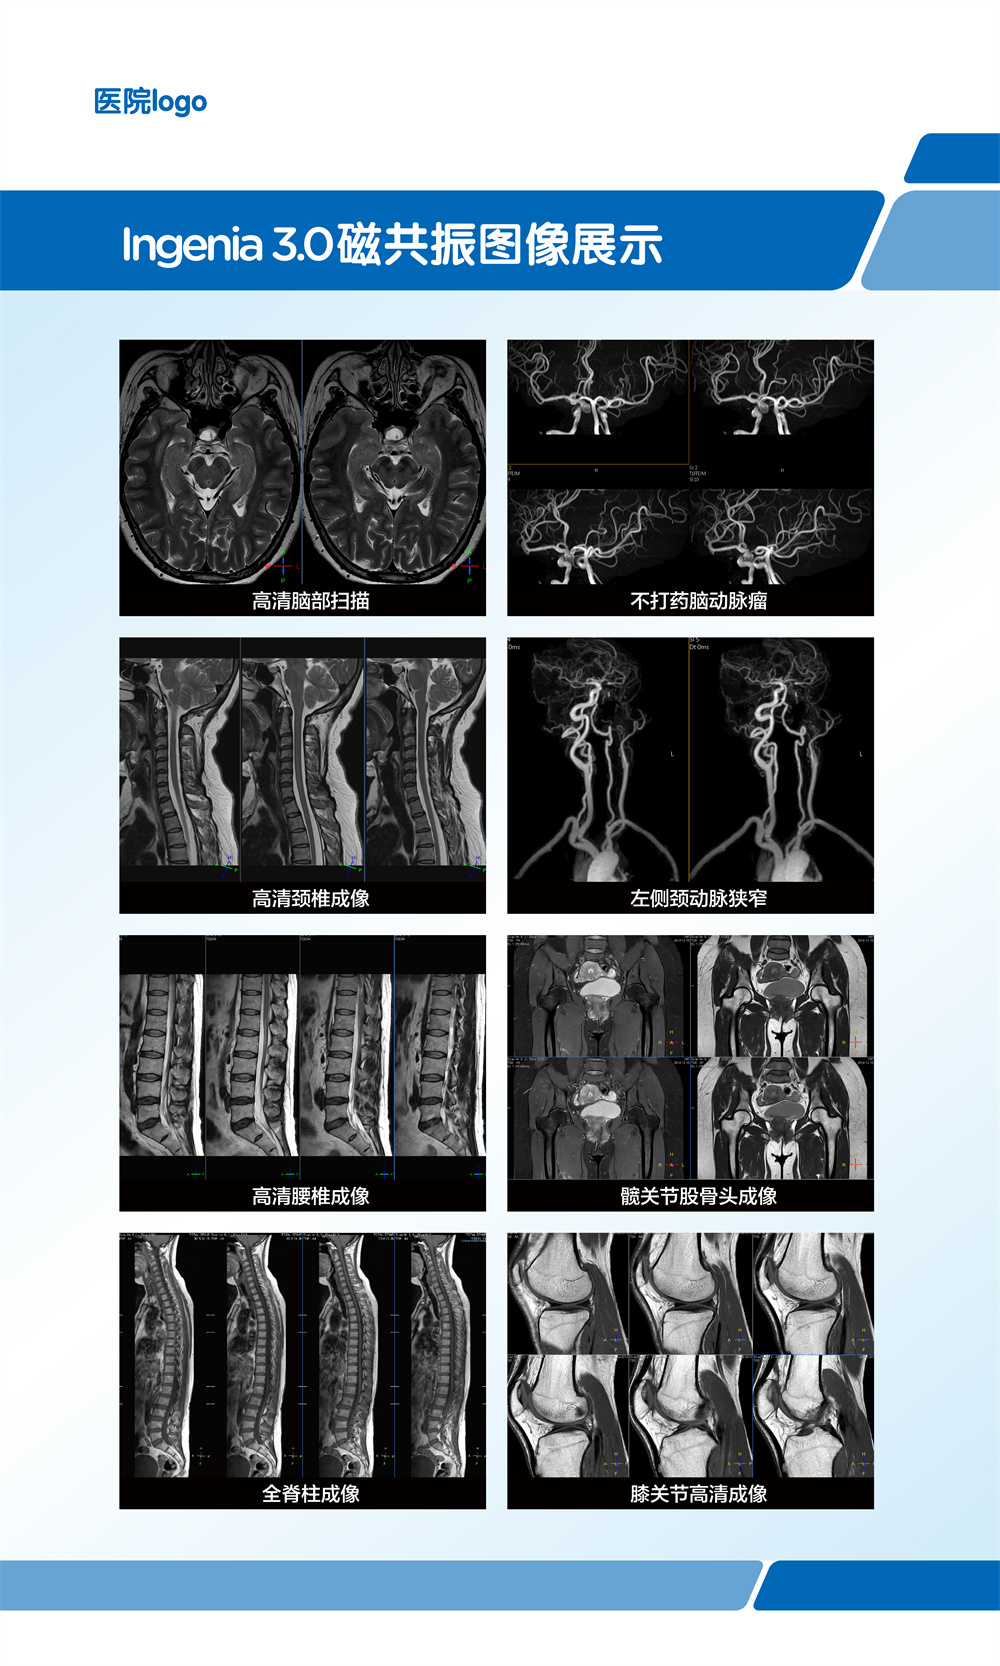

飞利浦大孔径光速Ingenia 3.0T磁共振是业内唯一同时具备"全数字高清成像平台和四维多源射频发射成像平台"的高端3T磁共振,具有病人检查舒适,扫描速度快,图像分辨率高的特点。在神经系统,骨肌系统,体部系统包括心脏和腹部等都有良好的应用和独到优势,为疾病的诊断及治疗提供更可靠、更丰富的信息,对于脑卒中和胸痛等中心的建设起到重要的作用。设备具备飞利浦独有的全数字线圈,可以实现三维全心不打药冠脉成像,无电离辐射和造影剂过敏风险,精准显示冠脉狭窄,有效排查临床无意义的冠脉狭窄(准确度达90%)。

磁共振冠状动脉检查无辐射,无需对比剂,对于缺血性心脏病,可以一次成像完整显示全心冠脉,便于直观诊断冠脉各分支情况。

在全身弥散加权成像的同时,可进行磁共振全身扫描,增加肿瘤检出敏感性。

临床应用范围:寻找恶性肿瘤原发灶;恶性肿瘤分期;全身转移灶筛查;淋巴结转移筛查;术后放化疗疗效监测;恶性血液肿瘤疗效观察;体检与肿瘤筛查。

亮血:血管狭窄筛查。黑血:血管壁斑块成像。

第三代无损加速磁共振成像-压缩感知(CS-SENSE),最快 32 倍加速,已将绝大部分临床成像转化为快速高清容积扫描。